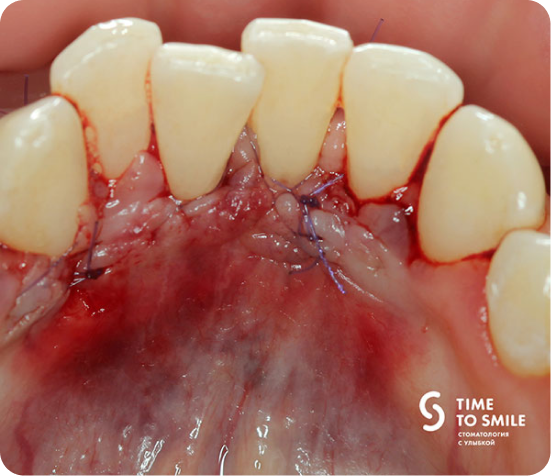

В ходе лечения проведена операция по закрытию дефекта с использованием десневого трансплантата из области твердого нёба.